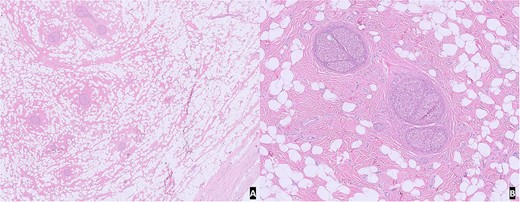

On gross examination, the specimen was composed of multiple fragments of yellow lobular adipose tissue, tan-pink soft tissue, and skin. No hemorrhage, necrosis, or discrete masses were identified. Microscopic examination of H&E slides from representative sections revealed unremarkable skin and subcutaneous tissue with benign nerve branches showing expansion of epineurium by adipose tissue and fibrous tissue. The morphological features were compatible with lipomatosis of nerve (Fig. 2).

H&E slide from representative sections: (A) low power view of unremarkable skin and subcutaneous tissue with benign nerve branches showing expansion of epineurium; (B) high power view showing expansion of epineurium by adipose tissue and fibrous tissue.